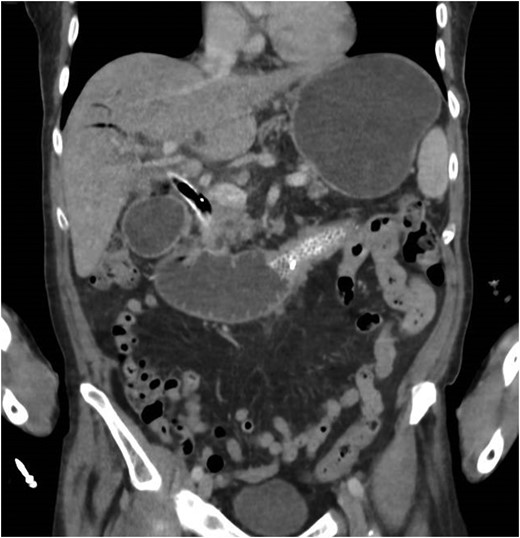

A CT scan (Fig. 1) reported duodenal obstruction secondary to tumour ingrowth. However, a subsequent gastrografin swallow performed 2 days later showed free passage of contrast through the duodenal stent without any hold up. On the basis of imaging result the patient was allowed to resume oral intake. During the admission the bilirubin started to increase and therefore on Day 18 of his admission (Bilirubin 130 ÎĽmol/l), a magnetic resonance cholangiopancreatography was performed. This revealed bilobar intrahepatic biliary duct dilatation without an obvious aerobilia, in keeping with biliary obstruction. The patient underwent an endoscopic retrograde cholangiopancreatography (ERCP) that demonstrated tumour ingrowth at the lower end of the biliary stent. An uncovered stent was successfully deployed to relieve the biliary obstruction.

CT scan showing gastric and duodenal dilatation down to the level of the stent suggesting obstruction at this level.